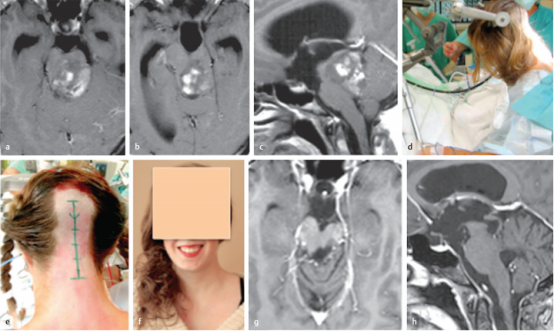

简要病史:20岁女孩由于背侧外生的中脑肿瘤引起的梗阻性脑积水而较度头痛。

术前:术前的轴位(a,b)和矢状位(c)对比增强MRI提示高级别肿瘤累及中脑和上脑桥。然而,由于患者没有神经功能缺损,肿瘤恶性程度似乎不太可能,并与患者及其家人讨论了低级别胶质瘤的可能性。

术中:d,e,患者同意并在半坐位进行手术干预;在整个手术过程中持续监测经食管超声心动图,以早期发现可能的空气栓塞。我们进行了枕下正中大骨瓣开颅术,肿瘤通过四脑室经远外侧入路进入。根据术中菱形窝定位,肿瘤位于左侧面神经丘上方。由于肿瘤与周围的脑干实质有很好的区分,肿瘤被完全切除并在术后MRI上证实。

术后:术后运动功能完好,仅抱怨轻度的六神经麻痹引起轻微的半感觉障碍和轻微的复视。组织病理学检查为WHO1级毛细胞星形细胞瘤。患者术后未接受辅助治疗,症状逐渐缓解。她的后续康复良好。术后多次MRI检查均未发现局部肿瘤复发或其他颅内异常。f,术后11年随访,患者的临床状况良好,眼球运动正常,右手手指有轻微的非干扰性感觉缺陷。在11年的随访中,轴位(g)和矢状面(h)MRI显示患者没有肿瘤残留或复发。

This 20-year-old woman had extreme headache due to obstructive hydrocephalus caused by a large dorsally exophytic midbrain tumor. At first glance, preoperative axial (a,b) and sagittal (c) contrastenhanced magnetic resonance imaging (MRI) was suggestive of a highgrade tumor involving the midbrain and upper pons. However, as the patient had no neurologic deficits, tumor malignancy seemed rather unlikely, and the possibility of low-grade glioma was discussed with the patient and her family. We offered her direct surgery without initially treating the occlusive hydrocephalus. (d,e) The patient agreed and underwent the surgical intervention in the semisitting position; transesophageal echocardiography was continuously monitored throughout the procedure for early detection of possible air embolism. A large median suboccipital craniotomy was performed, and the tumor was accessed via the telovelar approach through the fourth ventricle. According to the intraoperative mapping of the rhomboid fossa, the tumor was located superior to the left facial colliculus. As the tumor was well distinguishable from the surrounding brainstem parenchyma, gross total tumor resection was achieved and confirmed on postoperative MRI. While the patient’s motor function was fully intact after surgery, she complained only of slight hemisensory disturbance and minimal diplopia caused by mild sixth nerve palsy. Histopathologic examination revealed a pilocytic astrocytoma World Health Organization grade I. The patient received no postoperative adjuvant therapy, and her symptoms gradually resolved. Her further clinical course was uneventful. Repeated postoperative MRIs documented the absence of local tumor recurrence or other intracranial abnormality. (f) Eleven years after surgery, the patient was in excellent clinical condition and had normal eye movement and only minimal, nondisturbing sensory deficits in the fingers of her right hand. Axial (g) and sagittal (h) MRIs at 11-year follow-up show that the patient remains free of tumor remnants or recurrence.